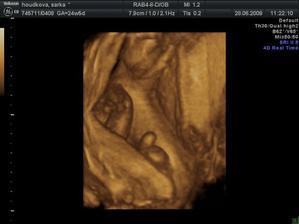

27.3 09 vyšetření screening dopdl dobře 🙂 miminko je zdravé má 11+5tt a 8cm žádná vývojová vada se nenašla. Jen placenta má rýhy jizvičky od hematomů,ale to prý nevadí to se zahojí.Hematomy už jsou pryč 🙂 28.5 Vyšetření a velký ultrazvuk ve 21tt dopadl dobře miminko zdravé vše bylo v pořádku , ukázal nám že to je kluk jako buk a váží už 413g .Také ve 21tt dává o sobě vědět už to není jen bublání v bříšku,ale semtam kopaneček a to tak dvakrát za den 🙂 4D ultrazvuk ve 25tt